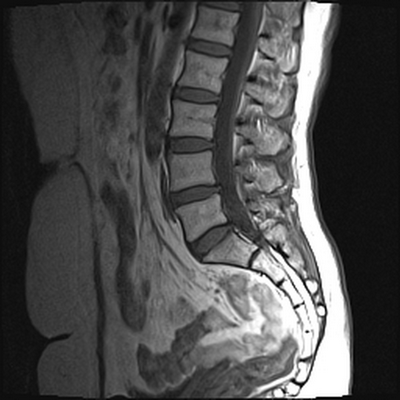

МРТ позвоночного столба: грыжа диска L4-L5 (сагиттальная плоскость, Т2 ВИ)

Магнитно-резонансное сканирование пояснично-крестцового отдела позвоночника: множественные гемангиомы (сагиттальная плоскость, Т1 ВИ)

МРТ: межпозвонковая грыжа диска L4-5 (аксиальная проекция, Т2 ВИ)